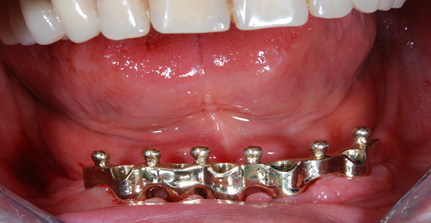

Protesi totale con mesostruttura avvitata su 5 impianti in un paziente edentulo